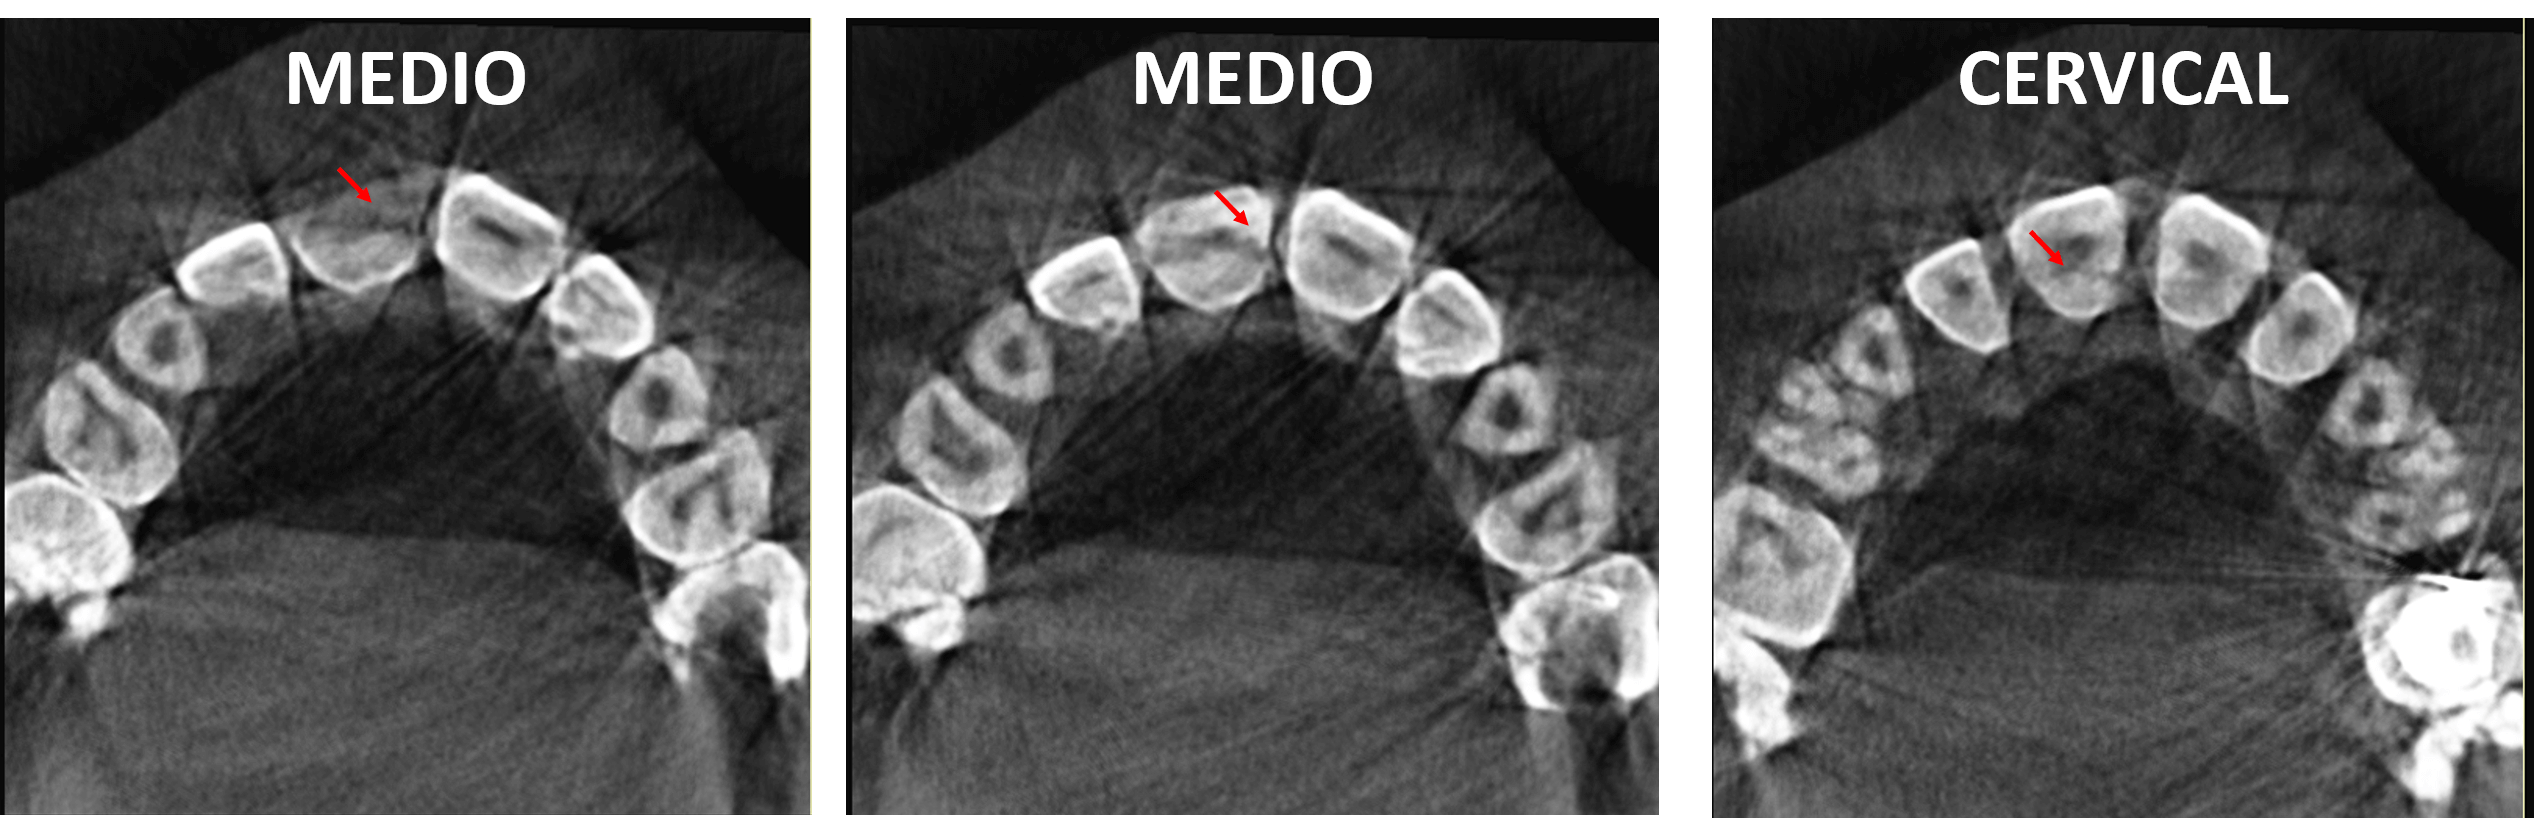

Fig.2

En cortes axiales (Fig.2) se observan la disposición mesiodistal de la fractura en los cortes que muestras el tercio medio radicular, comprometiendo la pulpa dentaria, y comprometiendo el tercio cervical coronario por palatino.